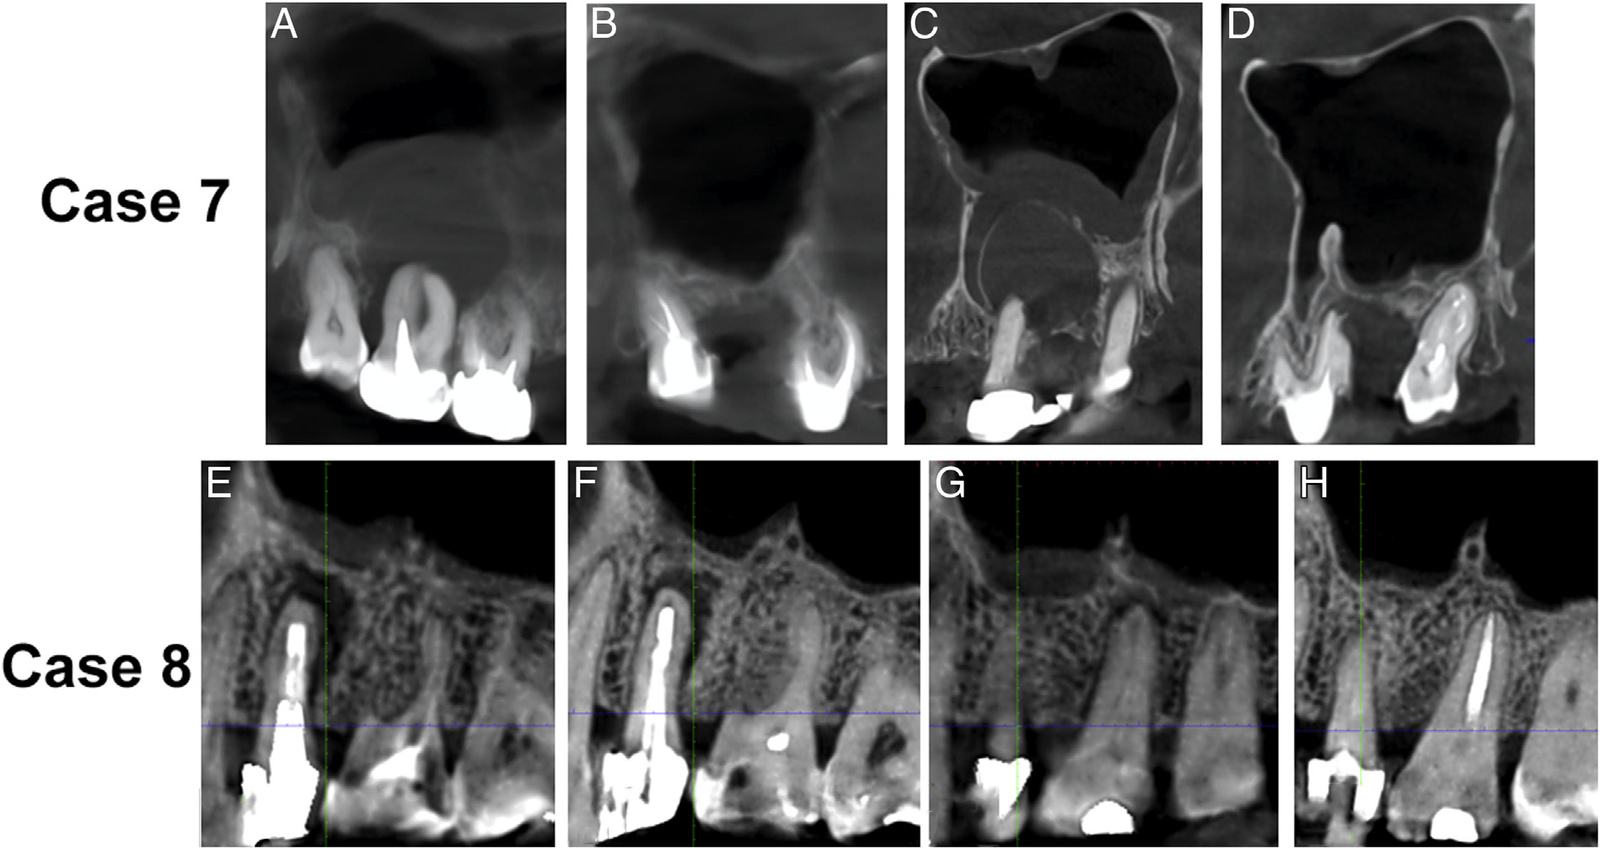

This article shows the follow-up of several cases of maxillary sinusitis of dental (usually endodontic) origin, with different manifestations, diagnostic challenges, and outcomes.Cases from 14 patients from 3 countries and treated by 7 different endodontists are presented, all of them with inflammatory sinus changes represented by mucositis, osteoperiostitis, and/or partial/full obstruction. All cases showed dental and/or sinus signs/symptoms that resolved after dental management. In 13 cases, the sinus condition had an endodontic origin, 4 of them concurrently with periodontal involvement. In 1 case, sinusitis was caused by trauma to the face. All cases but 1 had a satisfactory response of the periradicular tissues and maxillary sinus to treatment that consisted of root canal therapy, root amputation, extraction, or trauma management.The successful management of most cases reported in this article emphasizes the importance of endodontics as a specialty engaged in saving teeth and promoting health not only in the oral cavity but also in other areas that may be affected by infections of endodontic origin, including the maxillary sinus.